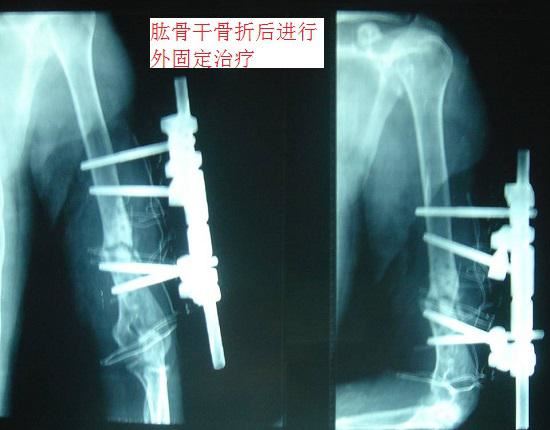

1、治疗手段。外固定是一种介于切开复位内固定(手术治疗)和保守治疗之间的骨折治疗手段,主要思路就是用克氏针等器械将移位部分复位,在骨折位置上下两端打入稳固装置(例如:钢钉)并通过体外支架连接,以实现骨折部位的固定(如下图所示)。肱骨骨折后外固定的治疗手段不需要进行大范围的软组织切开,还能够较好地保持断端对线,确保骨骼快速愈合;缺点在于外支架的?;は喽愿丛樱枰3至己玫乃山舳纫匀繁Q撕蜕窬橹δ?,;且要定期进行影像检查并调整对线。2、适应证。比较适用于开放型的、肱骨干部位的、伴有广泛软组织挫伤(或存在大范围感染)的肱骨骨折;较少用于肱骨头和肱骨近端的骨折。